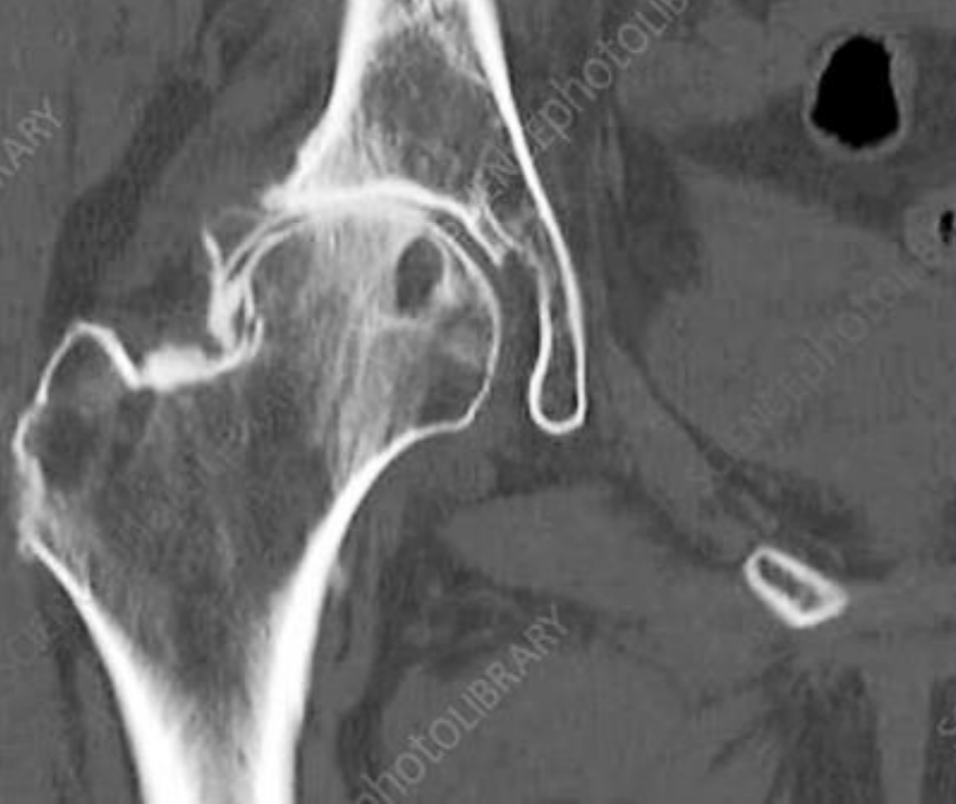

Datos de coxartrosis en TC

A

Mismo que Rx:Disminución del espacio articular

Osteofitos

Esclerosis subcondral

Quistes subcontrates (geodas)

Deformidad

Coxartrosis